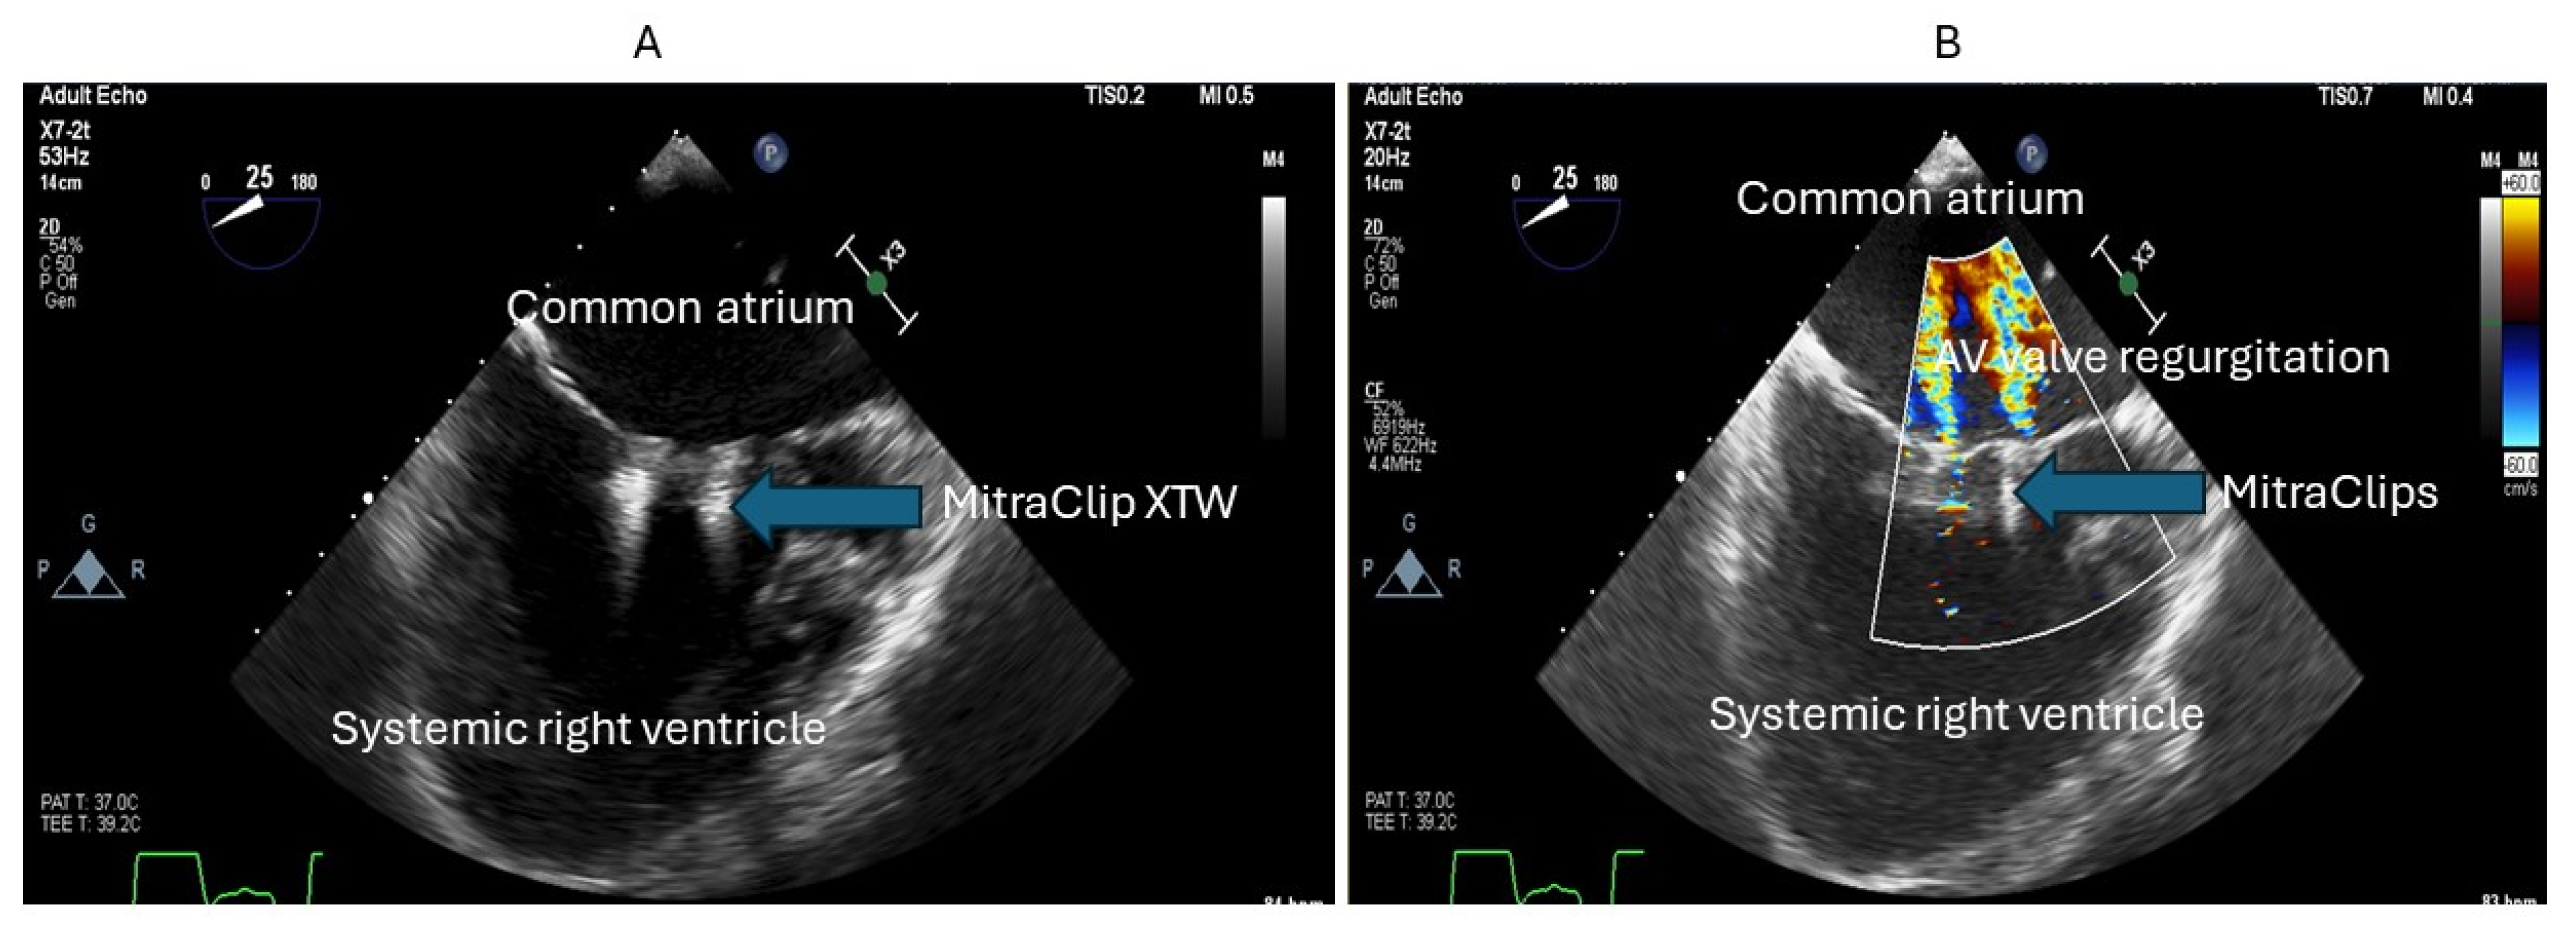

26. Selective Lymphatic Duct Embolization plus Covered Stent Placement

29. Percutaneous Intervention for AV Valve Regurgitation

- Kumar, P.; Gordon, B.M.; Kheiwa, A.; Abudayyeh, I. A case report of percutaneous MitraClip implantation in an adult with a double-outlet right ventricle. Eur. Heart J. Case Rep. 2023, 7, ytad247. [Google Scholar] [CrossRef] [PubMed]